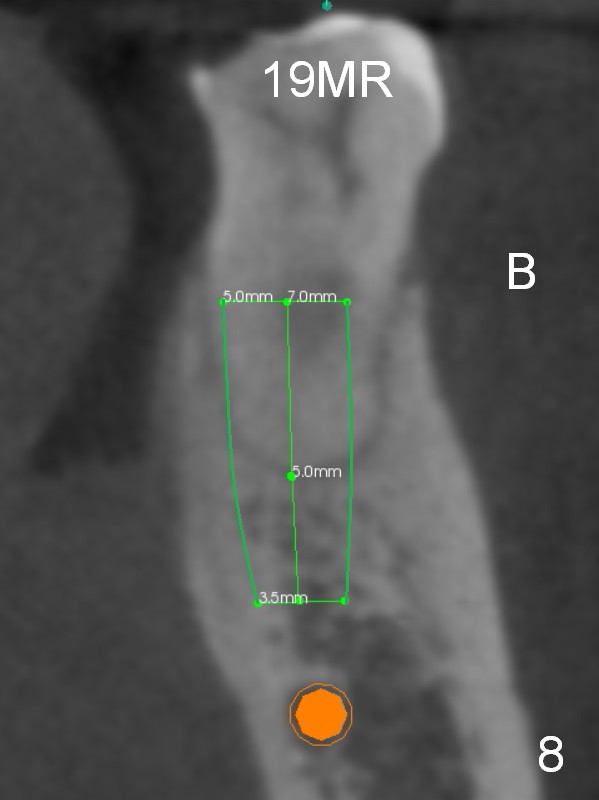

There is severe bone resorption around the distal root of the lower left 1st molar of the 56-year-old man (WG), while the loss of the 2nd molar is associated with limited bone height (Fig.1). A 5x14 mm implant will be placed at the mesial socket of #19 and 5.9 or 6.4x6 mm one is at the mesial site of #18 (Fig.7-9). Use a 2 mm pilot drill with 6 mm stopper from Sinus Master Kit (with extension) to initiate osteotomy at #18 immediately distal to the crown of #19, parallel to the long axis of the latter (Fig.2). After inserting a parallel pin at #18, extract the tooth #19 (Fig.3, antibiotic pending) and start osteotomy with a 2 mm pilot drill with 14 mm stopper (Fig.4). Insert the calibrated parallel pin at #19 (Fig.5) and measure the distance between the two parallel pins (approximately 10 mm, Fig.7). Sequential osteotomy and application of the Tatum taps (Fig.6 red rectangle) will push the septum distal (green arrow). As to #18 osteotomy, trephine, final and tap drills are to be used with control of the depth: 6 mm (Fig.7,9).